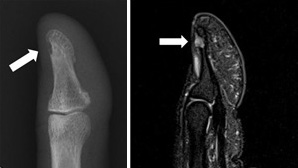

사구체종./사진=고대안암병원

사구체종은 5mm~1cm 정도로 크기가 작아 초음파 검사로 발견이 쉽지 않다. 정확한 진단을 위해 X-Ray로 피부와 뼈 구조를 확인하고, 사구체종이 의심된다면 MRI 촬영을 해봐야 한다. 사구체종이 발견되면 절제술을 진행해야 한다. 사구체 종양은 보통 손톱 밑과 뼈 사이에 있다. 일반적으로 수술은 손톱을 들고 종양을 제거한다. 수술 시간은 30분 정도다.